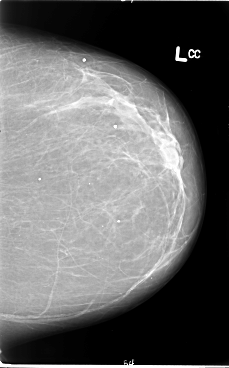

B_3065_1.LEFT_CC

LEFT_CC LINES 5880 PIXELS_PER_LINE 3664 BITS_PER_PIXEL 12 RESOLUTION 50 NON_OVERLAY